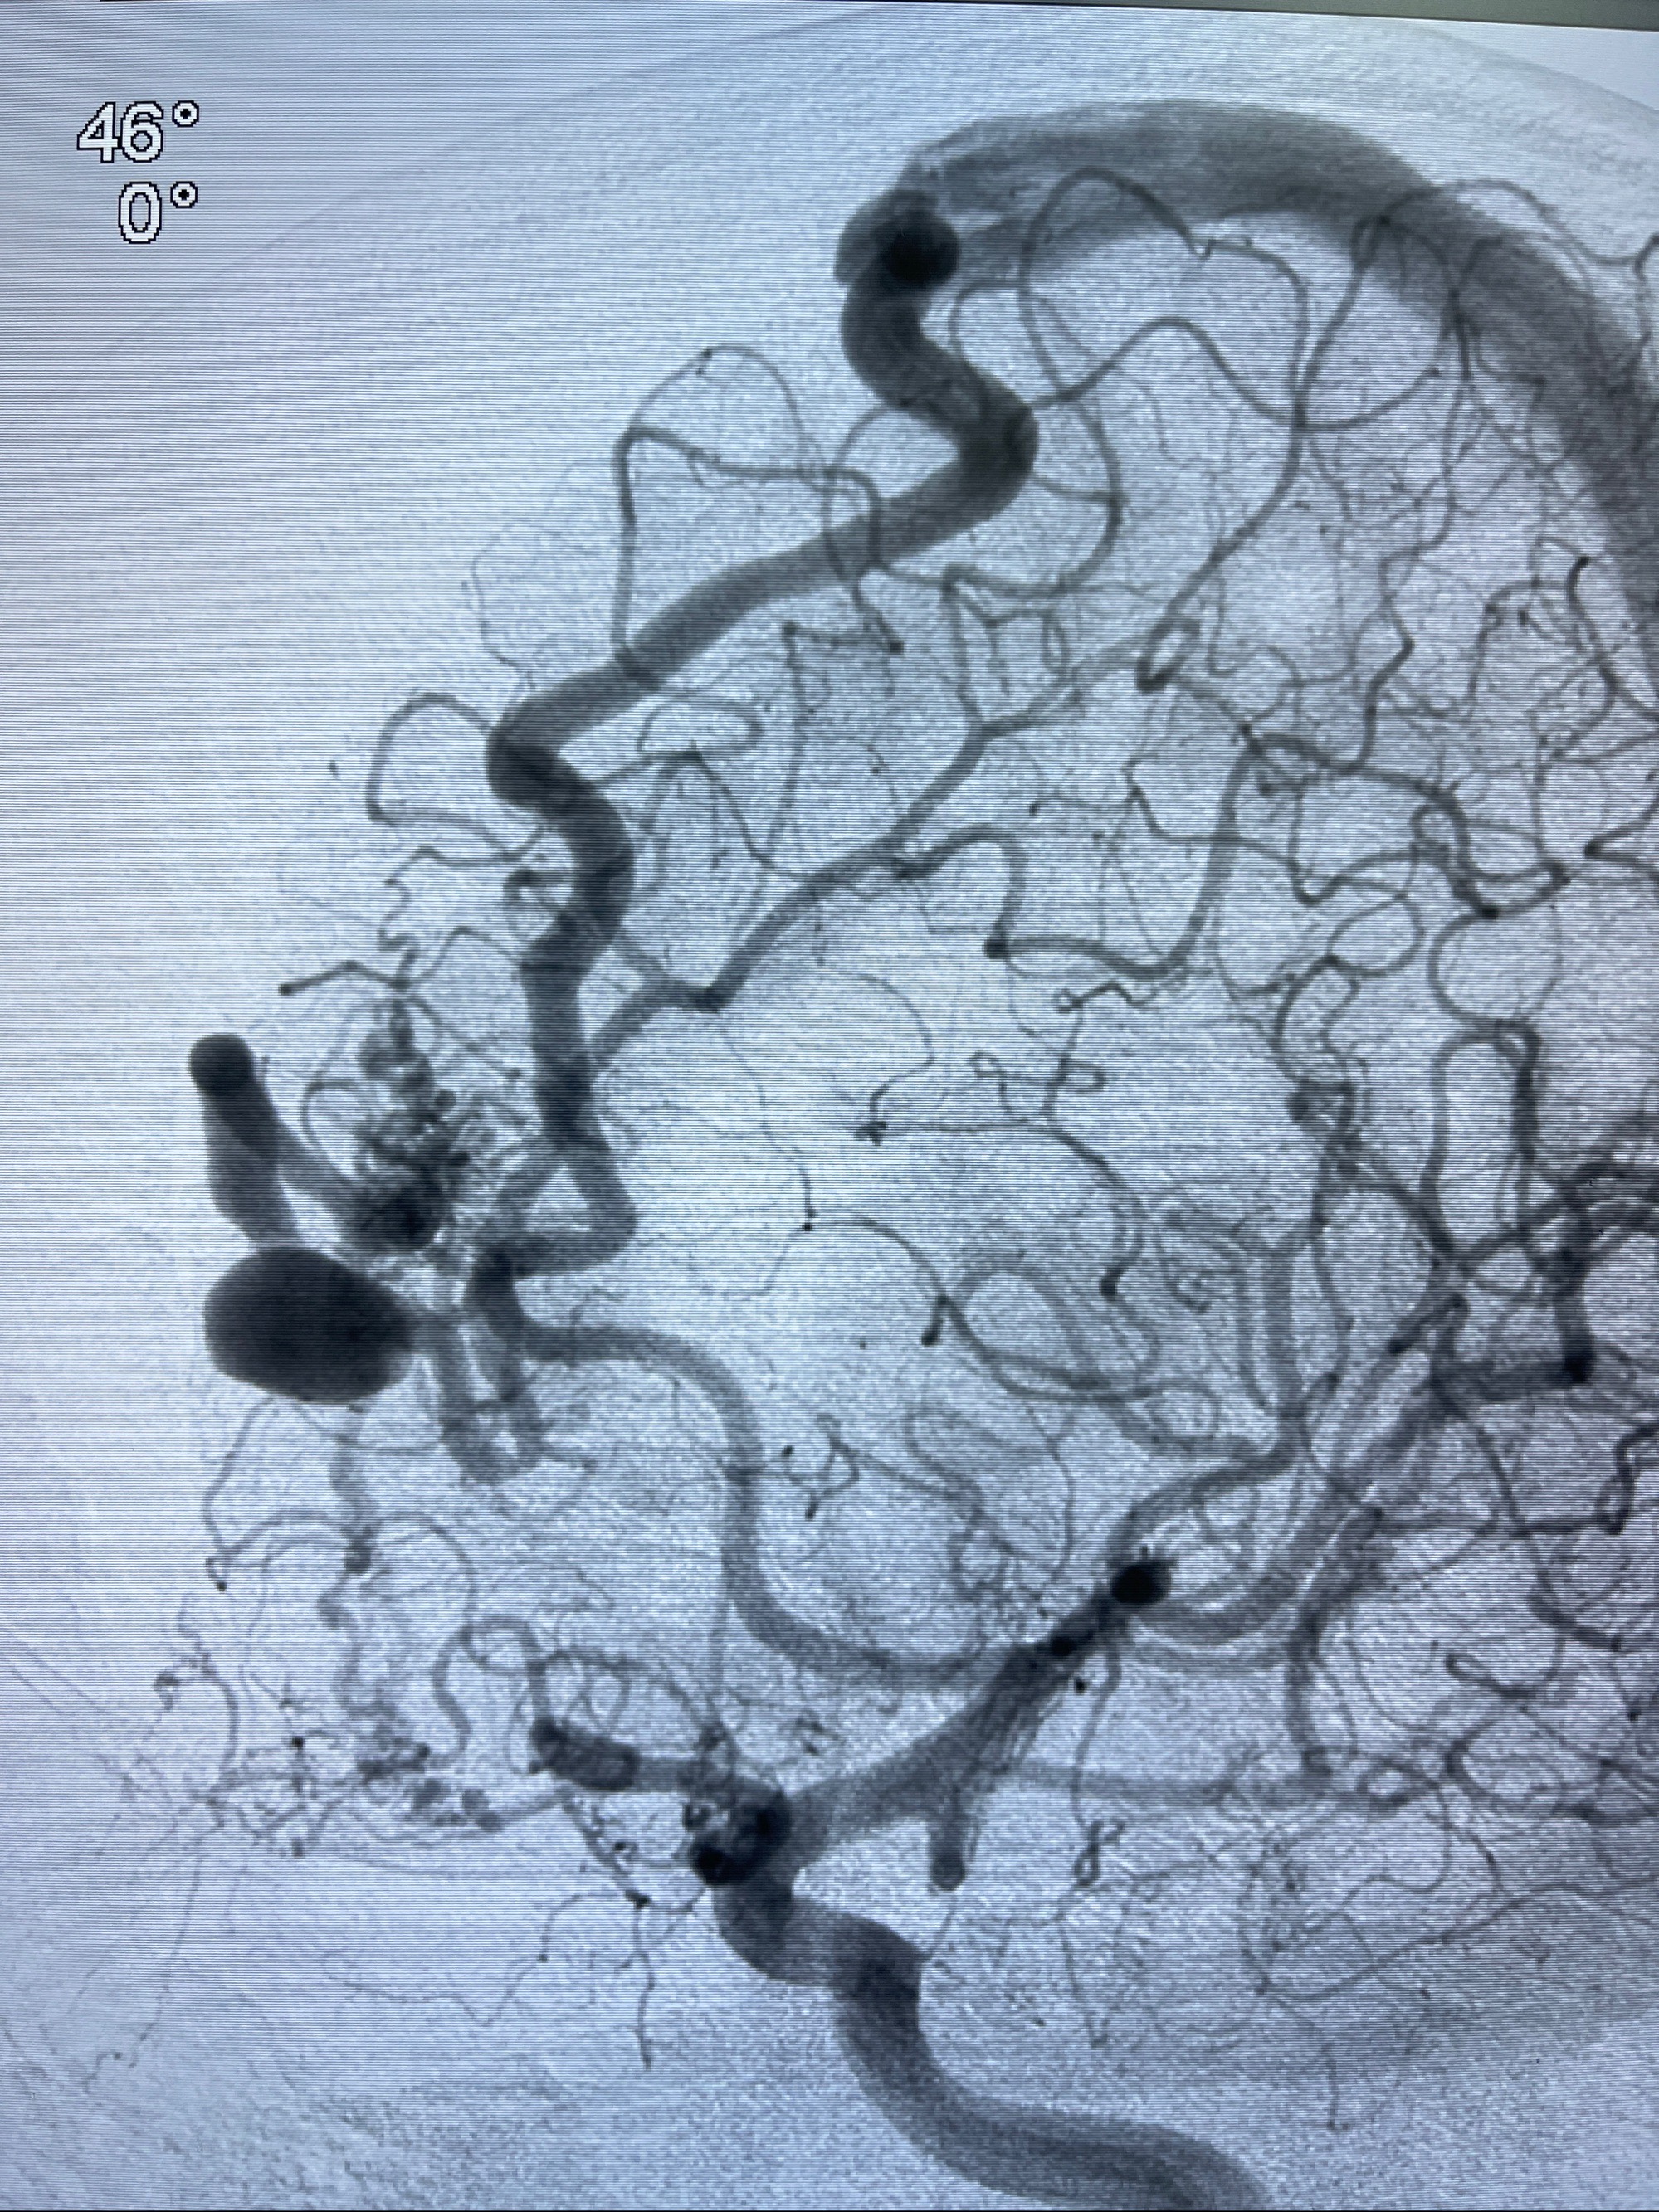

2023-09-13全脑血管造影:前颅底硬脑膜动静脉瘘,供血动脉为双侧胼周动脉、眼动脉脑膜支,静脉向上矢状窦方向引流

治疗策略:

- 外科手术?

- 介入干预:静脉途径栓塞or动脉途径填塞?